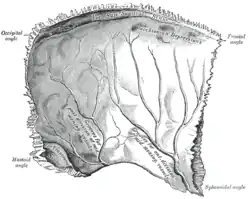

Left parietal bone. Inner surface.

On the inner surface of cranial bones, small pits called granular fovea are produced by arachnoid granulations.[3][4]